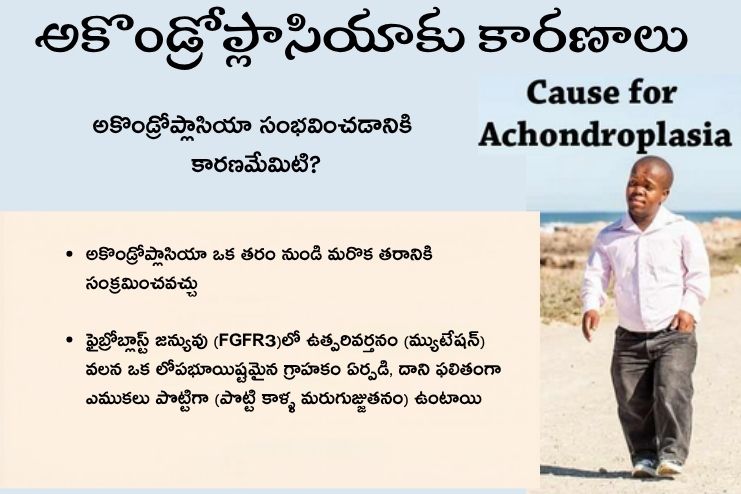

అకొండ్రోప్లాసియా యొక్క చాలా కేసులు వంశపారంపర్యంగా రావు. అకొండ్రోప్లాసియా ఎవరికైనా రావచ్చు. అకొండ్రోప్లాసియా ఉన్న వ్యక్తులలో సుమారు 80 శాతం మంది తల్లిదండ్రులు సాధారణ ఎత్తు ఉన్నవారై ఉంటారు. వారు ఒక కొత్త జన్యు మార్పుతో (డి నోవో మ్యుటేషన్) జన్మిస్తారు. ఈ తల్లిదండ్రులకు అకొండ్రోప్లాసియాతో మరో బిడ్డ పుట్టడం చాలా అరుదు. ఒక బిడ్డ అకొండ్రోప్లాసియాతో జన్మించడానికి తల్లిదండ్రులలో ఒకరు జన్యువును అందించినట్లయితే చాలు (ఆటోసోమల్ డామినెంట్). అకొండ్రోప్లాసియా ఉన్న వ్యక్తికి మరియు అకొండ్రోప్లాసియా లేని భాగస్వామికి ఈ రుగ్మతతో బిడ్డ పుట్టడానికి 50 శాతం అవకాశం ఉంది. తల్లిదండ్రులిద్దరికీ అకొండ్రోప్లాసియా ఉంటే, బిడ్డ హోమోజైగస్ అకొండ్రోప్లాసియాతో జన్మించడానికి 25 శాతం అవకాశం ఉంది. ఇది మృతశిశు జననానికి లేదా పుట్టిన కొద్దిసేపటికే మరణానికి దారితీస్తుంది.

పిండం అభివృద్ధి చెందుతున్నప్పుడు మృదులాస్థిని ఎముకగా మార్చే గ్రాహకంలో (రిసెప్టర్లో) జన్యు మార్పు (మ్యుటేషన్) జరగడం వల్ల అకొండ్రోప్లాసియా వస్తుంది.